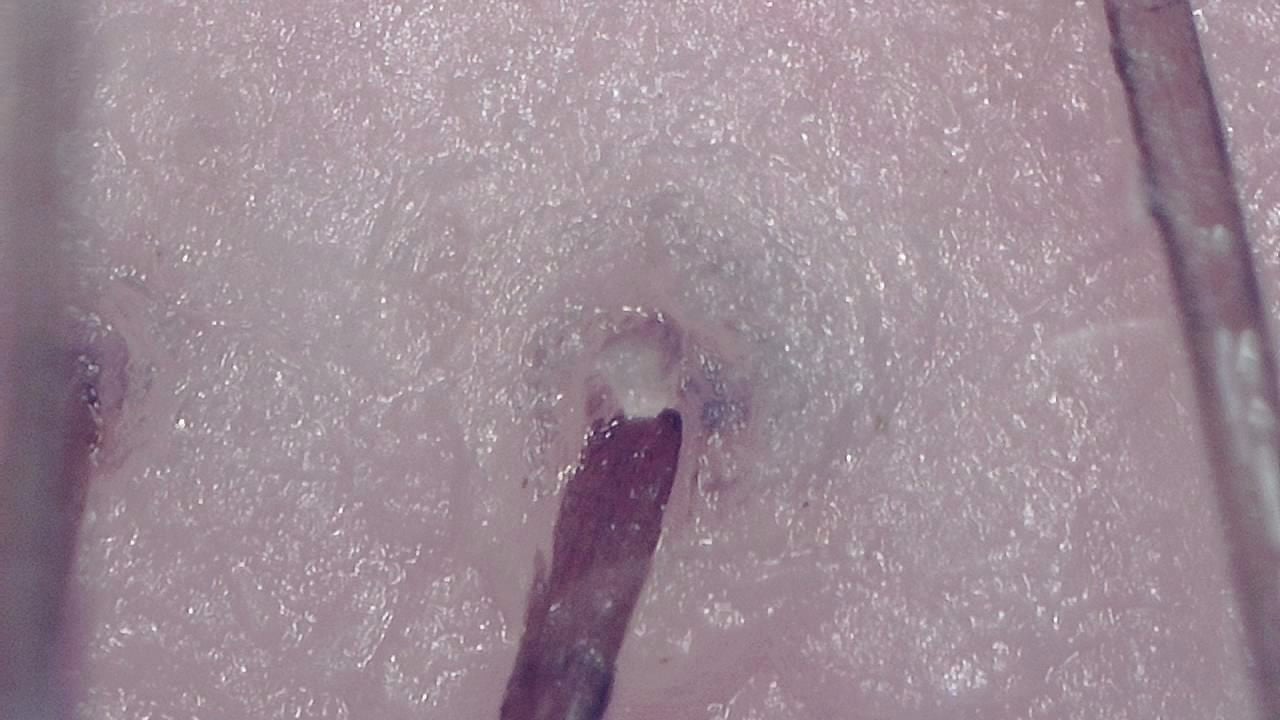

Early active alopecia areata diagnosis

A hair clinic detects exclamation mark hairs and black dots using Smart G-Scope trichoscopy, confirming active alopecia areata and enabling early treatment.